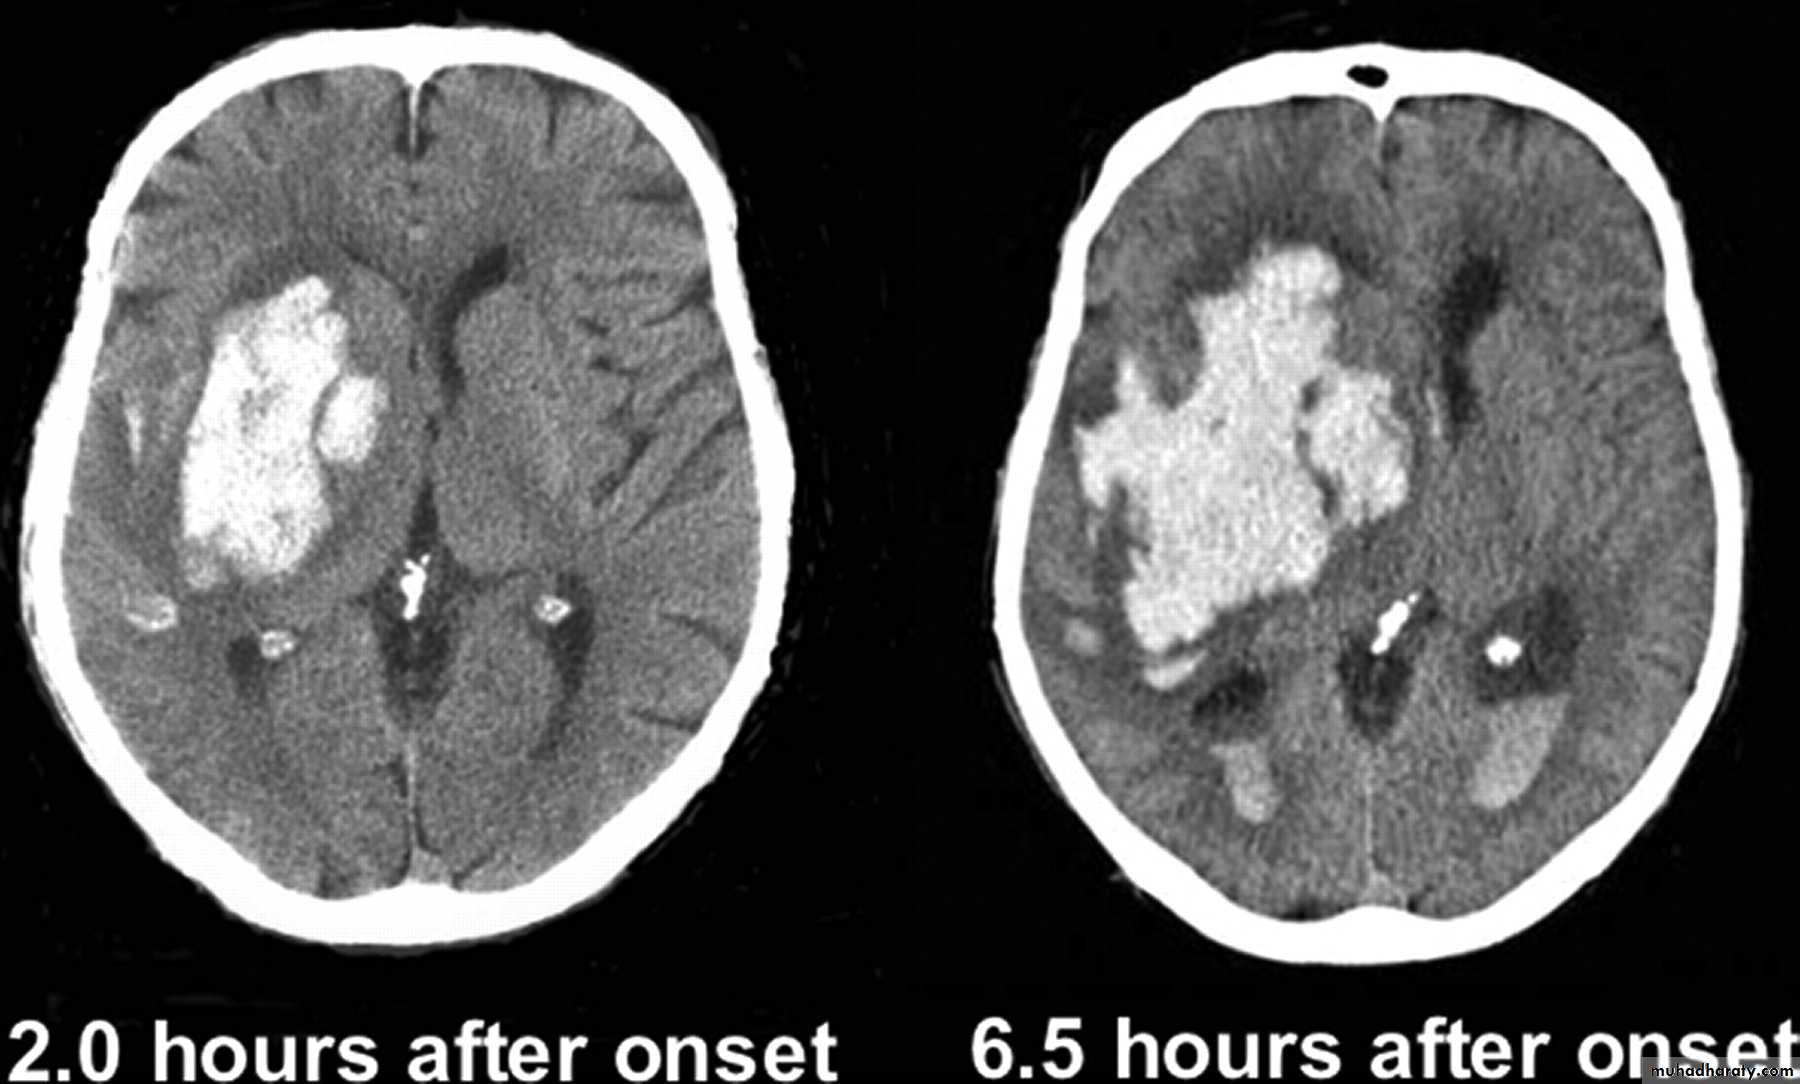

Common CT findings of traumatic brain injury